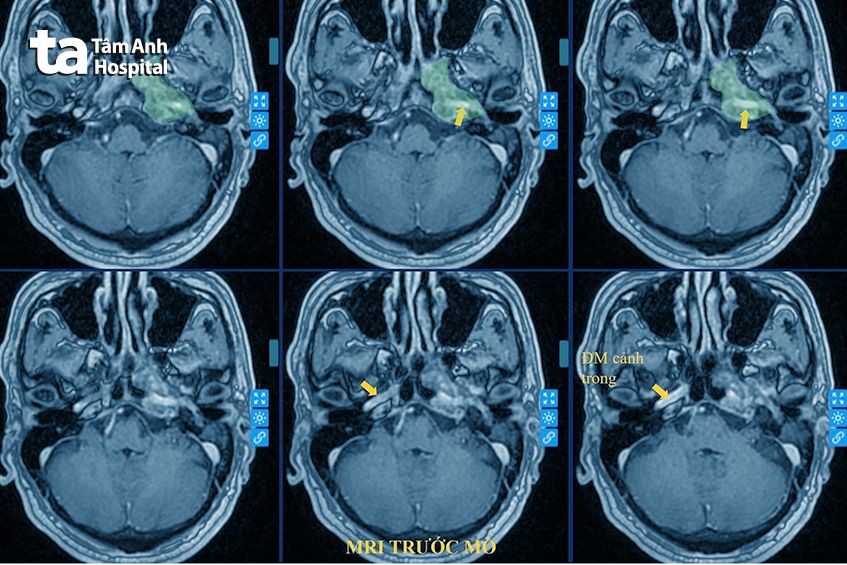

TS.BS Nguyễn Đức Anh, Trưởng khoa Ngoại Thần kinh – Cột sống, Bệnh viện Đa khoa Tâm Anh Hà Nội cho biết, người bệnh nhập viện trong tình trạng mất thính lực một bên tai, không kèm đau đầu hay yếu liệt. Kết quả chụp cộng hưởng từ (MRI) cho thấy khối u đám rối động mạch cảnh trong nằm sâu trong xương đá và xoang tĩnh mạch hang (cấu trúc giải phẫu vùng nền sọ thái dương, cực kỳ khó can thiệp). Khối u lan vào tai giữa, chèn ép động mạch cảnh trong và các dây thần kinh sọ não. Đây là loại u phát triển từ hệ thống thần kinh giao cảm, vốn điều khiển các hoạt động như huyết áp, nhịp tim, các tuyến nước bọt, tuyến tiết nhày của hầu họng, nằm sát mạch máu lớn ở nền sọ.

“Đây là một khối u rất hiếm gặp, y văn thế giới chỉ ghi nhận vài trường hợp tương tự. U xuất phát từ đám rối thần kinh quanh động mạch cảnh trong, nằm sâu trong nền sọ và có mức độ xâm lấn phức tạp. Do vị trí nền sọ phức tạp và gần mạch máu lớn, nguy cơ đột tử cao nếu không can thiệp.”, tiến sĩ Đức Anh nói.

Theo tiến sĩ Đức Anh, vị trí của khối u khiến ca mổ trở thành một trong những phẫu thuật nền sọ khó khăn và phức tạp. U không chỉ lan rộng trong xương đá mà còn bám sát, ôm vòng quanh thành động mạch cảnh trong (nguồn cấp máu chủ yếu của não). Chỉ một sai sót nhỏ cũng có thể dẫn đến hậu quả nghiêm trọng như vỡ mạch, gây chảy máu ồ ạt, tổn thương các dây thần kinh, hoặc hẹp, tắc mạch não gây nhồi máu não nặng, thậm chí có thể tử vong ngay trên bàn mổ.